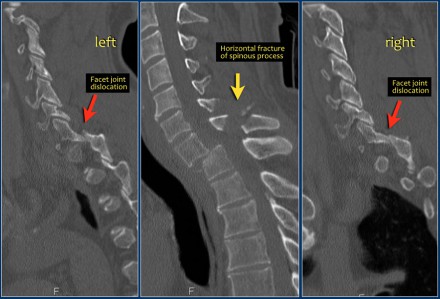

In this case of translation there is bilateral facet dislocation and also a horizontal fracture of the spinous process.

There is severe narrowing of the spinal canal.

The findings are:

- Morphology: Distraction- 4 points

- PLC: always disrupted in distraction on posterior side - 3 points

- TLICS: 7 points